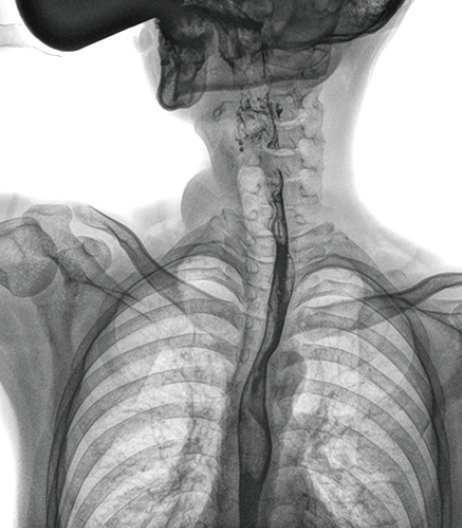

食管造影是食管病变的基本检查方法,可以发现食管癌的特征性改变——食管粘膜的中断和破坏,病人常感觉吞咽障碍,此特征在临床中最常见,也是早期食管癌的典型表现。一般伴随的特征有管壁充盈缺损、龛影、软组织块影、食管腔狭窄等;在透视下还可看到食管壁僵硬、蠕动缓慢等。

在食管造影检查中,由于吞咽钡剂后,造影剂流速非常快,动态DR影像采集幅面大,普利德多功能动态DR 17×17英寸超大视野,一次曝光即可显示整个食管,更方便观察食管的病变,确定病变的范围,对诊断和治疗有重要参考价值。

动态 DR 可以动态观察管壁蠕动是否僵硬,以鉴别良、恶性狭窄,不但在透视过程中,可实时高清点片,实现毫秒级动静态图像切换,快速捕捉病变部位的影像,成像清晰而迅速,尽可能减少食管功能性障碍患者因吞咽困难而忍受痛苦的时间,同时提高医生做出正确诊断的效率,还能实时保存视频影像,反复观察、分析,明确病变范围,对手术有重要的指导意义。

与过去的数字胃肠机比较,动态DR图像分辨率高,对食管的全景观察,局部粘膜破坏、中断,管腔狭窄以及病灶范围的显示清晰度明显更优。